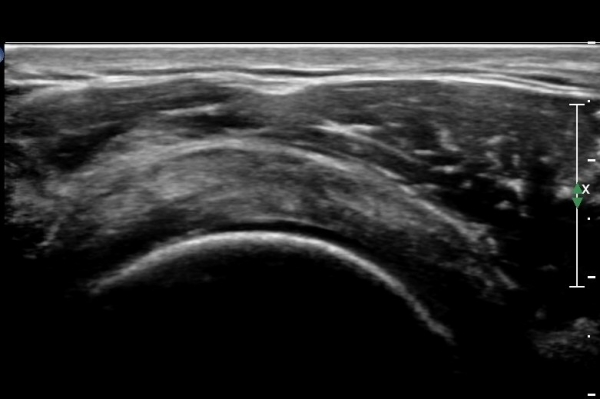

°ßºÀÈ¸Ãø Ãæµ¹ÁõÈıº°Ë»ç(°íÂû »çÁø Âü°í)¿¡¼­ °ßºÀ¿ÜÃø¿¡ ¼ö¾×ÀÌ Àú·ùµÇ°í °Ë»ç ½Ã

°ßºÀ ¾Æ·¡¿¡¼­ ÀâÀ½(crepitus)ÀÌ ´À²¸Áü.(»çÁø 6).